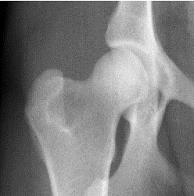

當前主流的骨關節保健品主要有葡萄糖胺(glucosamine)、軟骨素(chondroitin),以及有機硫同化物(methyl-sulfonyl-methane,即MSM)等。葡萄糖胺和軟骨素在骨關節處形成蛋白聚糖,吸收水分和體液,使關節運動時得到潤滑,而MSM則是止痛劑。這些都僅僅是緩解症狀,很難治本。美國UCLA骨科專家臨床研究表明,一般葡萄糖胺要四、五年才能修復軟骨;而以II型骨膠質(kolla2)為主方,輔以上葡萄糖胺、MSM等,則大大縮短消除關節疼痛和修復軟骨的時間。研究證明服用II型骨膠質(kolla2)六周后,患有髖關節發育異常的犬科動物恢復了正常運動功能,隨後的X-射線檢查表明其髖關節軟骨恢復正常。

服用骨膠質Kolla2之前

服用骨膠質Kolla2之後一些非類固醇類消炎藥物如喜樂保(celebrex)和威克適(vioxx)曾被廣泛使用於骨折病人和骨關節炎病患,使其減少關節疼痛。而2004年以來,越來越多的研究發現這些藥物除了止痛之外並不能改善病人的骨骼健康,反而加長了骨折恢復期,並增加腦中風、心臟病發作的危險。2005年4月,美國FDA勒令以上各種藥物下櫃。II型骨膠質(kolla2)完全不含任何西藥止痛藥成份,2005年上市以來,迄今沒有發現任何一例毒副作用報告。